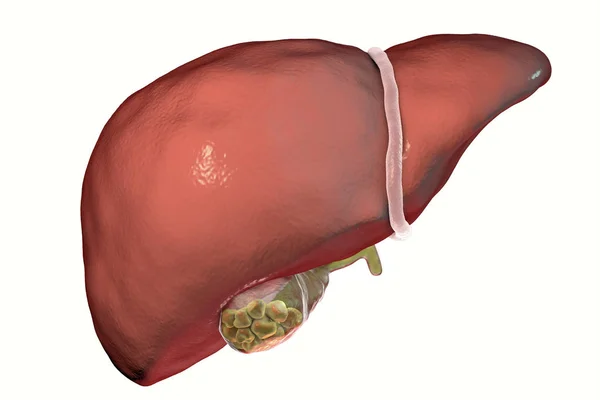

Опухоль Печени Фото

Опухоль Печени Фото 116 фото